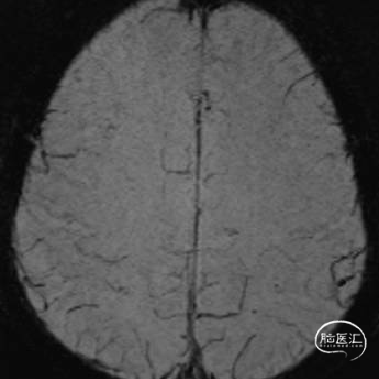

头部SWI

2、该病例为颈内动脉起始处重度狭窄,有颈动脉支架置入指征;术前评估左侧颈内动脉起始处呈多节段、溃疡性斑块,病变相对较长,术中避免输送器材过程中出现斑块脱落;头颅灌注提示左侧颞叶、放射冠区域缺血代偿期改变,头SWI未见微出血灶,提示发生高灌注风险相对较低,可充分抗板治疗,但术后仍需严格控制血压。术前置入临时起搏器,避免术中出现心率下降甚至骤停风险。